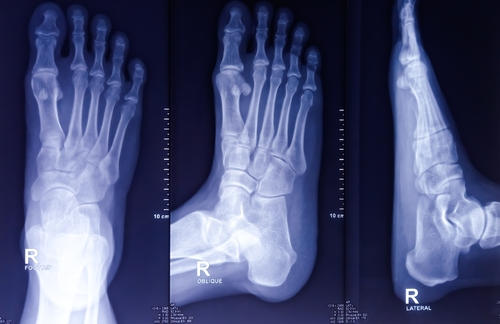

Чаще всего проводится рентген стопы в двух проекциях (боковой, прямой). Во время рентгена в прямой проекции человек лежит на спине. Ноги сгибает в коленях и ставит их на стол. При боковом рентгене стопы пациент ложится на бок. Пораженная конечность лежит на кассете. Иногда осуществляется рентген стопы в косой проекции. Человек лежит на спине. Ноги согнуты. Изучаемая конечность повернута на нужный угол.

Расшифровка результатов

Во время расшифровки результатов доктор изучает полученные изображения. Оценивает видимые структуры, сравнивает готовые данные с рентгеном стопы в норме. Доктор диагностирует разные нарушения. Определяет их протяженность, параметры, внешний вид, очертания, характер поражения и другие особенности. Специалист пишет детальное заключение. Указывает верные рекомендации.

Что видно на рентгене стопы?

Посредством рентгенограммы ступни выявляют:

- остеофиты;

- аномалии развития;

- артроз;

- признаки подагры;

- нарушение целостности костей;

- остеосклероз;

- вывихи;

- трещины;

- инородные предметы;

- остеопороз;

- плоскостопие;

- артрит;

- асептический некроз;

- гнойные процессы;

- опухоли (доброкачественные, злокачественные);

- очаги метастаз;

- косолапость;

- вальгусную деформацию первого пальца.